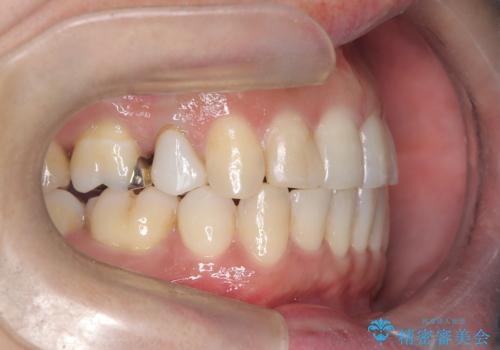

- 治療計画

- 治療計画: 重度の叢生を改善するため、上下左右の小臼歯抜歯を伴う審美ワイヤー矯正を計画しました。抜歯により得られたスペースを利用して歯を整列させ、適切な噛み合わせを目指します。途中、患者様が1年間の海外出張となったため、一時的にワイヤーを外し、保定装置で現状維持を図りました。帰国後に再度審美ワイヤー矯正を再開し、仕上げ調整を行い治療完了を目指します。

重度の叢生により、抜歯を伴う矯正が必要と判断しました。目立ちにくい透明な審美ブラケットを用いたワイヤー矯正を実施しましたが、治療途中での海外出張が決定したため、一度矯正装置を取り外し、保定装置で現状維持を行いました。帰国後に改めて装置を装着し矯正を再開。患者様のライフスタイルに柔軟に対応しながら、最終的には理想的な歯並びと美しい口元を実現しました。